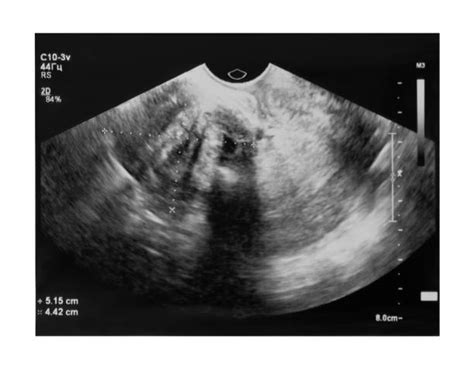

Ultrazvukové vyšetrenie

Ultrazvuk je v súčasnosti najspoľahlivejšou a najčastejšie používanou metódou na diagnostiku AIP. Rozsiahle metaanalýzy preukázali vysokú senzitivitu (takmer 91 %) a špecificitu (96 %) ultrazvukového vyšetrenia pri identifikácii AIP. Typické ultrazvukové nálezy zahŕňajú:

- Ztráta alebo prerušovaná hypoechogénna zóna medzi placentou a myometriom (normálne je prítomný zreteľný priestor).

- Zvýšená vaskularizácia v oblasti rozhrania medzi serózou maternice a stenou močového mechúra.

- Prítomnosť placentárnych „jazierok“ alebo lakún: Viacpočetné lineárne nepravidelné vaskulárne priestory v placente, ktoré jej dodávajú vzhľad „švajčiarskeho syra“.

- Fokálna alebo difúzna intralakunárna prietoková aktivita pri Dopplerovskom vyšetrení.

- Cievne „ostrovčeky“ s turbulentným prúdením.

Ultrazvukové nálezy môžu byť prítomné už v prvom trimestri, najmä ak je plodové vajce nidované v dolnom segmente maternice, blízko alebo v mieste predchádzajúcej hysterotomie. Farebné Dopplerovské mapovanie a volumové ultrazvukové zobrazenie môžu pomôcť pri spresnení diagnostiky.